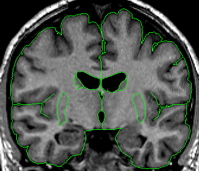

|  | The putamen is a subdivision of the lenticular nucleus (the other division is the pallidum). The lenticular nucleus from the axial view resembles a rounded triangle that is divided into two major sections. The putamen is the lateral part of this triangle.The putamen starts small and ends small in the coronal view. The putamen quickly grows to its greatest size in the middle and in the medial posterior portion it closely resembles a goldfish shape. The putamen lies lateral and partially anterior to the thalamus. It is bordered laterally, superiorly, and inferiorly by white matter. The putamen is usually bordered medially by the pallidum. When the pallidum is not yet present or has already disappeared the putamen is bordered medially by the internal capsule. | |

It is important not to include the claustrum in the putamen; this is the strip of tissue bordering the lateral edge of the putamen. Often the putamen can be extracted at the same time as the caudate especially in the area where they are connected by the nucleus accumbens. The histogram of the caudate, in many cases, is close to what you want for the putamen as well. After extracting the caudate, before deleting the remaining red lines, you can often go immediately into the intensity contour function and adjust them to fit the putamen.  This should be done separately for each hemisphere. | ||

| Labeling The final outline should be labeled as "putamen," and any blood vessels extracted should be labeled as "vessel." | ||